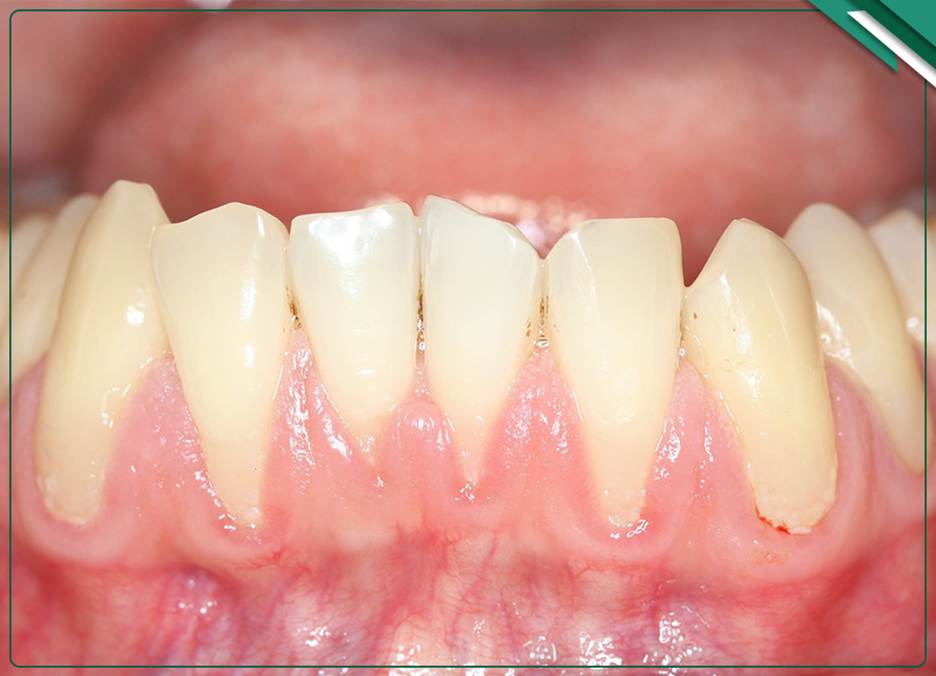

تحلیل لثه چیست؟ کاهش بافت لثه و نمایان شدن ریشه دندان

تحلیل لثه به معنای کاهش بافت لثهای است که دندانها را دربرمیگیرد و منجر به نمایان شدن ریشه دندان میشود. این وضعیت باعث حساسیت دندانها، التهاب و افزایش خطر پوسیدگی ریشه خواهد شد و سلامت دهان را به خطر میاندازد. تحلیل لثه در بیماران تحت درمان ارتودنسی، به ویژه در فرآیندهای پیچیده مانند ارتودنسی دو فک که نیازمند مراقبتهای دقیقتر است، اهمیت بالاتری دارد. این عارضه نهتنها باعث کاهش زیبایی لبخند میشود بلکه بر نتیجه نهایی درمان و هزینه ارتودنسی دو فک نیز تاثیرگذار است. شناخت دقیق تحلیل لثه برای ارائه درمان مناسب و حفظ سلامت طولانیمدت دندانها ضروری است.

تحلیل لثه در حین ارتودنسی که به آن پسروی یا عقبنشینی لثه (Gingival Recession) نیز گفته میشود، یکی از عوارض جانبی احتمالی این درمان است. اگرچه این پدیده برای همه رخ نمیدهد، ولی مجموعهای از عوامل بیولوژیکی و مکانیکی ریسک وقوع این اتفاق را افزایش میدهند:

بیوتایپ (ضخامت) لثه بیمار: افراد با لثههای نازک و حساس (بیوتایپ نازک)، بهطور ذاتی مقاومت کمتری دارند و در برابر حرکت دندان یا التهاب، بسیار مستعد تحلیل لثه هستند.